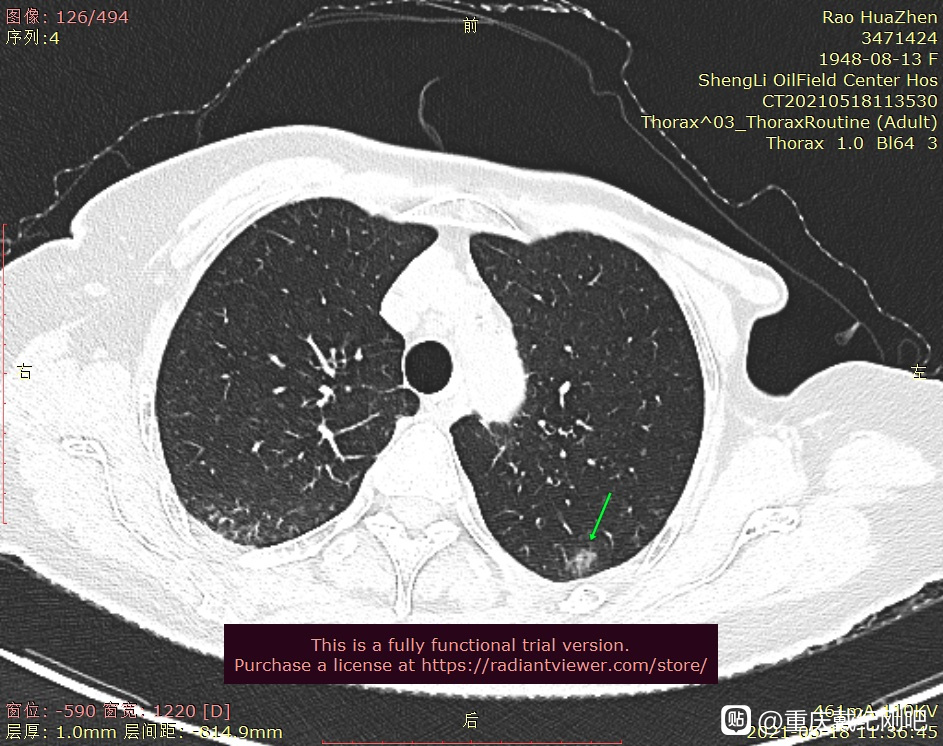

我母亲曾做过胃间质瘤手术,18年乳腺癌手术,5月18日复查发现双肺多发磨玻璃结节,最大的11毫米,请戴主任百忙之中用您的火眼金睛给出诊断和治疗意见,我也是您曾经面诊过的磨玻璃结节随访患者,是拉萨妹和fay妹指导我通过邮箱找出有结节的部位,希望我没操作出错,期盼您的回复。

很像早期浸润性腺癌,左侧的结节手术。右侧的结节随访,不长大不管。目前手术估计也可以治愈。